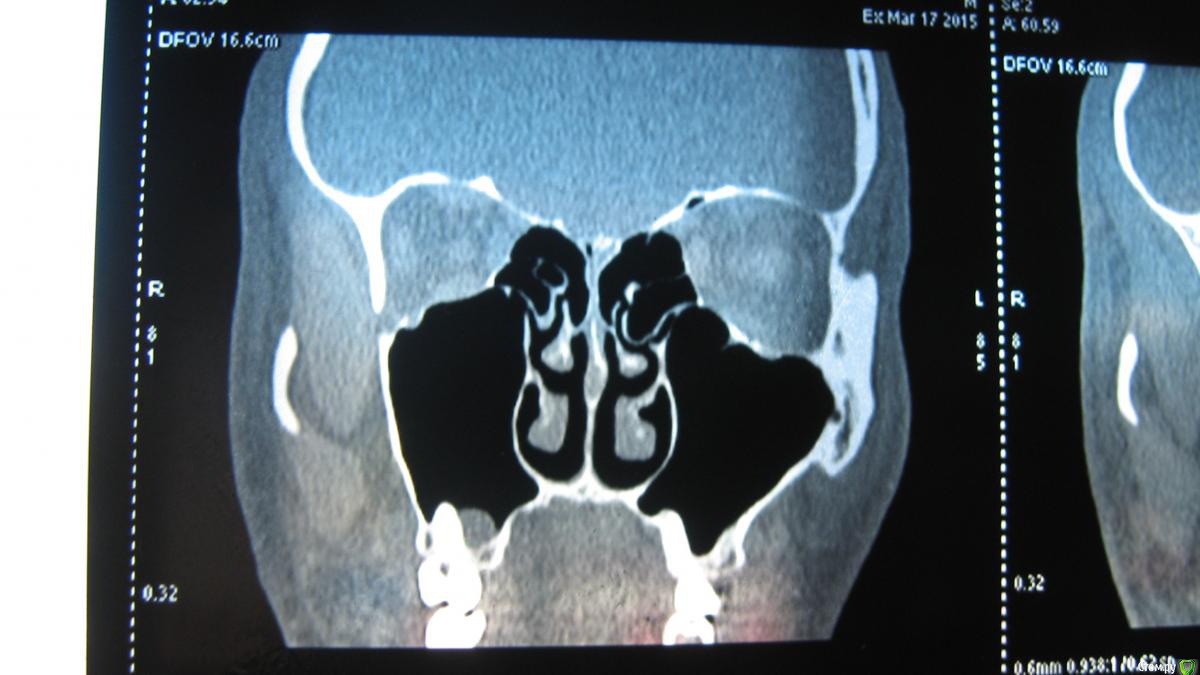

sasha35 Опубликовано 21 марта, 2015 Поделиться Опубликовано 21 марта, 2015 Здравствуйте. Осенью 2014 года лечил 4 зуб вверху. На 2 день после установки пломбы была боль, которая прошла через несколько дней. Со временем обнаружил, что больно нажимать на верхушку корня. Сам по себе не болит.Сделал снимок зуба, сходил к стоматологу. Он сказал, что плохо запломбирован канал. Я отказался вскрывать зуб. Сейчас появилась необходимость сделать СКТ ППН (для испр. носовой перегородки). Обнаружена киста в/ч пазухи, с той стороны где этот зуб(7*8мм) Сделал панорамный снимок челюсти, пошел к челюстно-лицевому хирургу. Он на снимке ничего не нашел. Тоже сказал, что зуб плохо запломбирован и возможно идет воспаление. Кисты на снимке нет. Может такое быть, на СКТ киста есть, а на рентгене нет? Выходит либо кистане связана с зубом, либо на СКТ воспаление показало как кисту? К кому мне обращаться? Ссылка на комментарий

sasha35 Опубликовано 22 марта, 2015 Автор Поделиться Опубликовано 22 марта, 2015 СКТ и рентген зуба. Панорамного снимка нет. Ссылка на комментарий